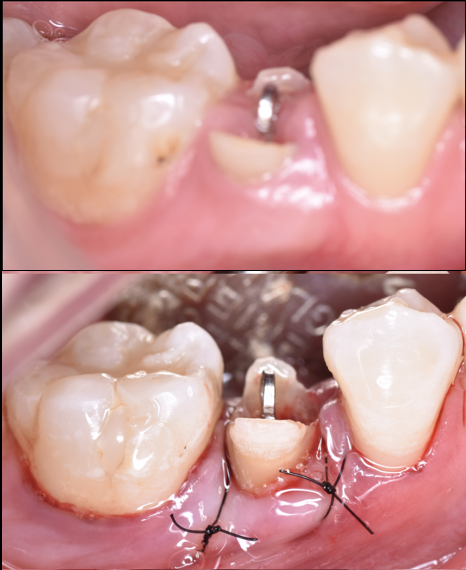

【グランドメゾンデンタルクリニック】抜歯後の骨...

[池袋 歯医者]歯の移植〜インプラントをする前に...